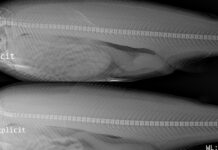

Virussykdommen PD rammer fiskens bukspyttkjertel, og er blant de mest alvorlige sykdommene for oppdrettslaks i Norge. Smittet fisk kan slutte å spise, og sykdommen fører derfor til redusert tilvekst.

Den kroniske sykdommen BKD (bakteriell nyresyke) er en annen alvorlig sykdom som kan ramme norsk laks. BKD fikk en kraftig oppsving i 2023 med tolv påviste utbrudd, og så langt i år er det påvist fem utbrudd av sykdommen.

ILA angriper fiskens blodårer, og kan derfor føre til alvorlig anemi og sirkulasjonsforstyrrelser.